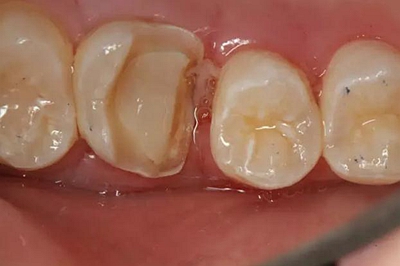

患者男性,35歲,B6銀汞充填后食物嵌塞,要求重新充填,口內檢查見B6近中鄰頜面銀汞充填物,局部缺損,有繼發(fā)齲,去除原充填物及繼發(fā)齲,發(fā)現齲壞位于牙齦下方,給予冠延長手術,同期嵌體預備,后一次性取模。(同樣設計為齦上邊緣)

硅橡膠取模后,灌注模型,科爾琥珀樹脂制作嵌體。